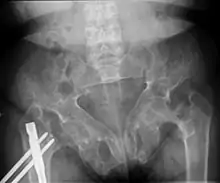

Brown tumors in the pelvis and a hip fracture.[18]